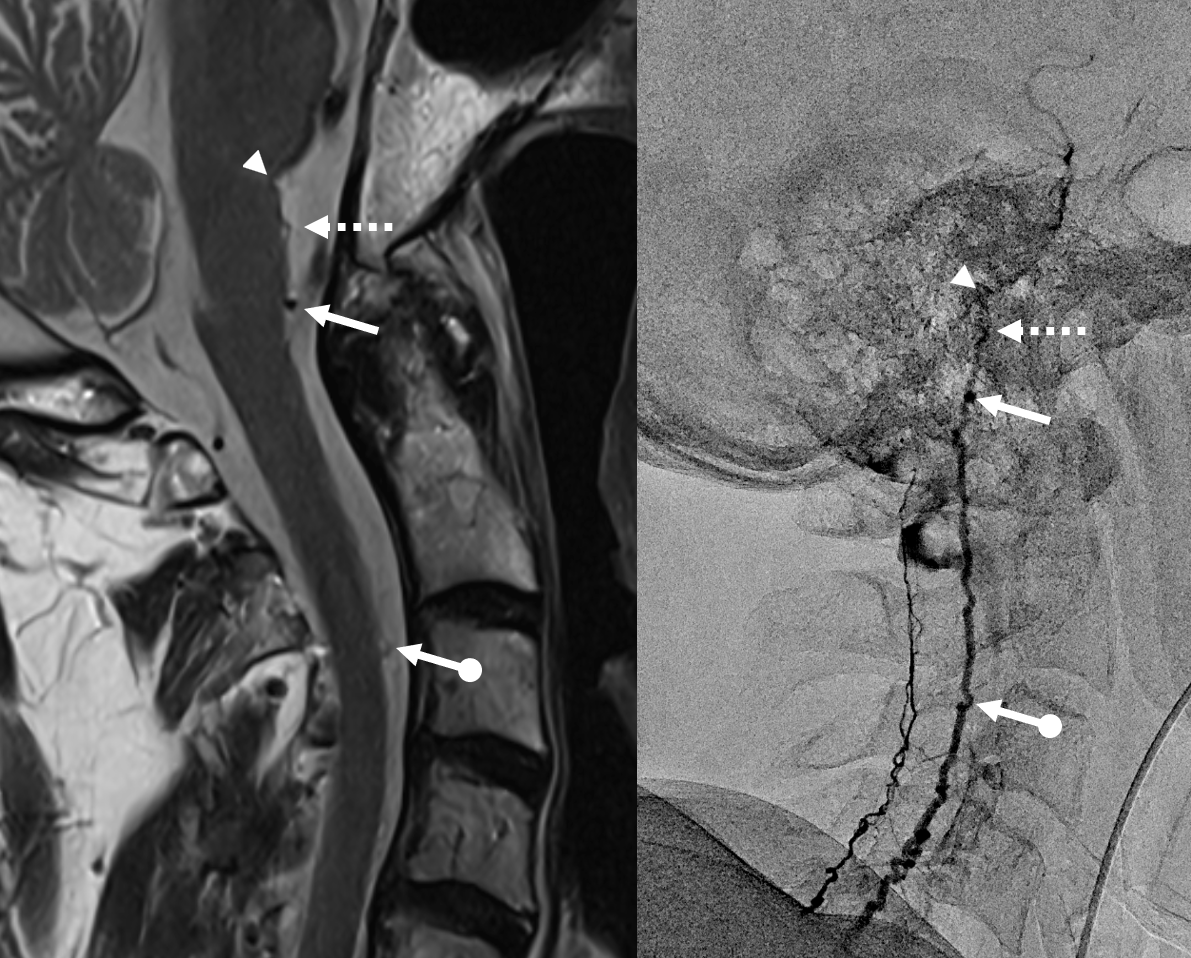

All dural fistula pathophysiology, and spinal too, consists of two key factors. One is fistula. The other is degree of venous congestion. Normal spinal venous anatomy consists of multiple radicular veins which drain the cord via nerve root sleeve / foramen into the epidural venous plexus. These veins are almost always deficient (missing from getgo, thrombosed, both?) in patients with spinal dural fistulas. Could it be that venous deficiency comes first, and fistula emerges later? Probably not, but interesting to consider. In any case, good spinal angiography involves imaging of fistula runoff to see extent of congestion and where drainage finally happens. In this case, there are no radicular veins in lumbar or thoracic cord at all. Not until the foramen magnum/C1/C2 do we see any outflow, and that is insufficient as well — with congestion extending all the way up to basal vein! Note perfect visualization of anterior pontomesencephalic and interpeduncular veins. When it finally reaches basal vein, the outflow is diluted by cranial venous tributaries.

In retrospect, corresponding veins on MRI and angio

Very important to find both dominant radiculomedullary supply to the lower cord (aka Adamkiewicz) and posterior spinal arteries. In the Adamkiewicz injection, there is usually no venous phase due to fistula-related congestion. In this case, not only we dont see veins, we also don’t see the conus basket. That is frequently seen from posterior spinals, except in this case we did not see posterior spinals either. That is a concern since we don’t want to inadvertently embolize them. However, given the congestion the most likely explanation is that the basket normally opacifies from the Adamkiewicz / ASA, and is congested by fistula.